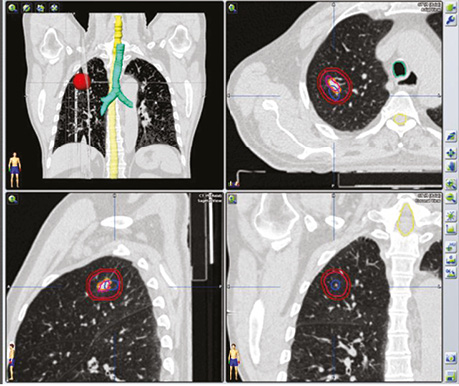

В якості ілюстрації наводимо клінічні випадки виконання ПЕТ / КТ з 18F-ФДГ у хворих з йод-негативними вогнищами ДРЩЗ з метою діагностики та постлікувального моніторингу.

Хворий А., папілярний рак щитоподібної залози, 4 курси РЙТ, відсутність накопичення 131I-NaI на постлікувальному скані після 3-го курсу. За даними УЗД та КТ обстеження — підозра на можливі вогнища в зоні шиї та легень. Хворому назначено ПЕТ / КТ з 18F-ФДГ (рис. 4, 5).

У пацієнта Б. з фолікулярною формою ДРЩЗ на постлікувальному скані після 5 курсу РЙТ відмічалася відсутність накопичення 131I-NaI. При цьому за даними КТ та високими показниками ТГ можна було передбачити можливість метастазування. Хворому рекомендовано ПЕТ / КТ з 18F-ФДГ (рис. 7).

Рис. 7. ПЕТ / КТ з 18F-ФДГ. Візуалізується вогнище в лівій легені

На КТ-зображенні відмічається чітке вогнище в лівій легені, яке збігається при накладанні метаболічного ПЕТ-скану. Інші дрібні вогнища відповідають фіброзним та кальцинатним утворенням.

Отже, на етапі одержання структурного зображення вже була отримана інформація про наявність метастатичного вогнища в легені, яка була підтверджена за допомогою 3D-трансформації (рис. 8).

Рис. 8. Трансформація зображення — метастатичне вогнище в легені

Наступним етапом була таргетна терапія йод-негативного метастатичного вогнища в легені. Для оцінки результативності лікування проведено ПЕТ / КТ з 18F-ФДГ. За даними метаболічного сканування достовірних змін як щодо розмірів вогнища, так і ступеня його функціональної активності не виявлено.